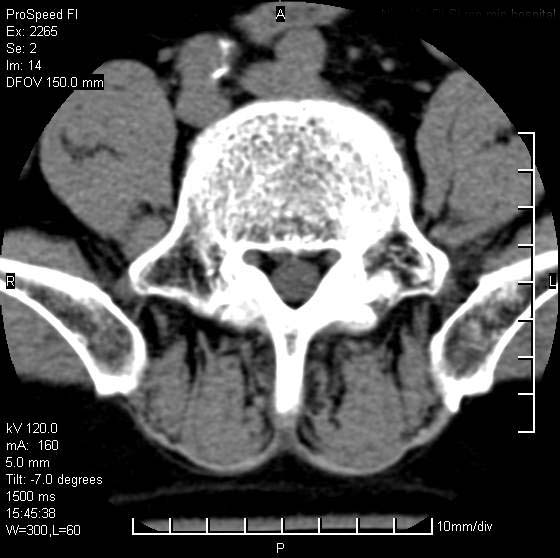

以下是引用qiushi在2007-8-22 17:26:00的发言:[br]没骨窗![br] 1、 l5~s1间盘膨出伴轻度突出(中央型)、变性。[br] 2、l4~5间盘膨出伴突出(右侧远外侧型)。[br] 3、l3~4间盘膨出。[br] 4、腰椎退行性变。[br]

以下是引用随缘的人在2007-8-22 20:56:00的发言:[br]腰椎退行性变:1。l4/5,l5/s1膨出[br] 2。l5/s1间盘退行性变 [br] 3。腰椎骨质增生

以下是引用liaizhi在2007-8-22 22:13:00的发言:[br]1,l4-5锥间盘膨出,2,l5-s1椎间盘膨出并退变(椎间盘呈真空征);3,血管瘤(椎体骨小梁稀疏粗大)?